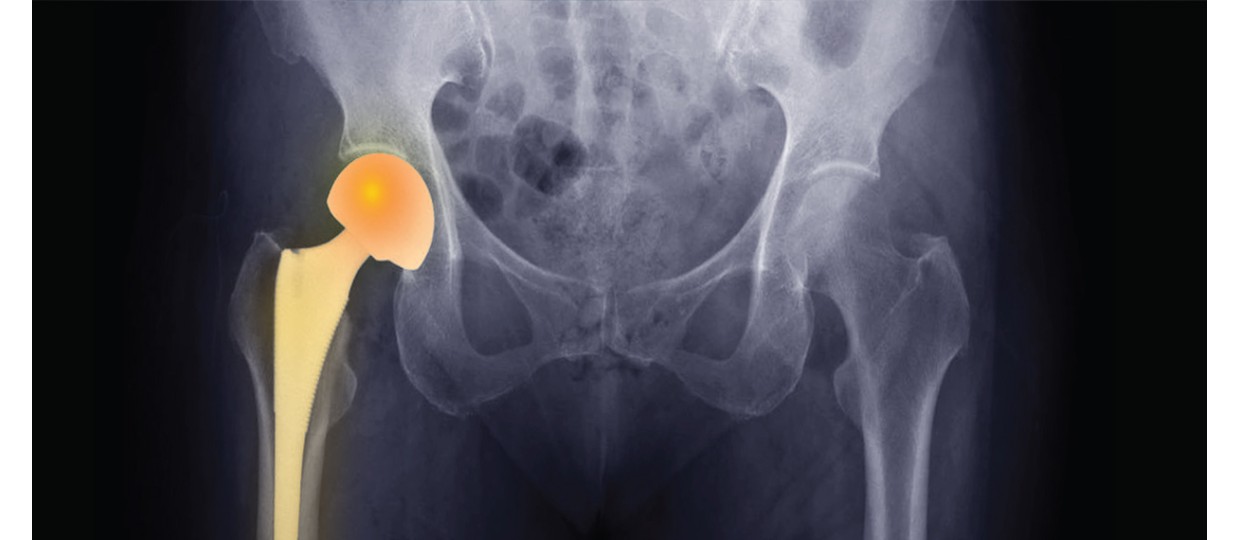

Una prótesis de cadera es un implante médico diseñado para reemplazar una articulación de la cadera que ha sido dañada por diversas causas, como artrosis severa, fracturas, necrosis avascular o enfermedades inflamatorias. Su objetivo es aliviar el dolor, recuperar la movilidad y mejorar la calidad de vida del paciente.

Este procedimiento quirúrgico se conoce como artroplastia total de cadera y es una de las intervenciones más efectivas y seguras en cirugía ortopédica.

- Prótesis total de cadera: reemplaza tanto el acetábulo (parte de la pelvis) como la cabeza del fémur. Es el tipo más común.

- Prótesis parcial (hemiartroplastia): reemplaza solo la cabeza femoral. Se suele usar en algunos tipos de fracturas en pacientes mayores.